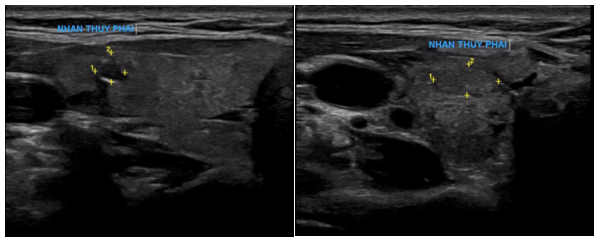

Siêu âm:

Thùy phải: kích thước bình thường, nhu mô có vài nhân hỗn hợp âm, lớn nhất kích thước 3x3mm và có nhân giảm âm, vôi hóa ngoại vi kích thước 3x4mm (TIRADS 4), nhân đồng âm bờ đều, kích thước 4x6mm.

Thùy trái: kích thước bình thường, nhu mô có vài nhân hỗn hợp âm, bờ đều, lớn nhất kích thước 8x9mm (TIRADS 3).

Hình 1: Hình ảnh nhân giảm âm thùy phải tuyến giáp (TIRADS 4)